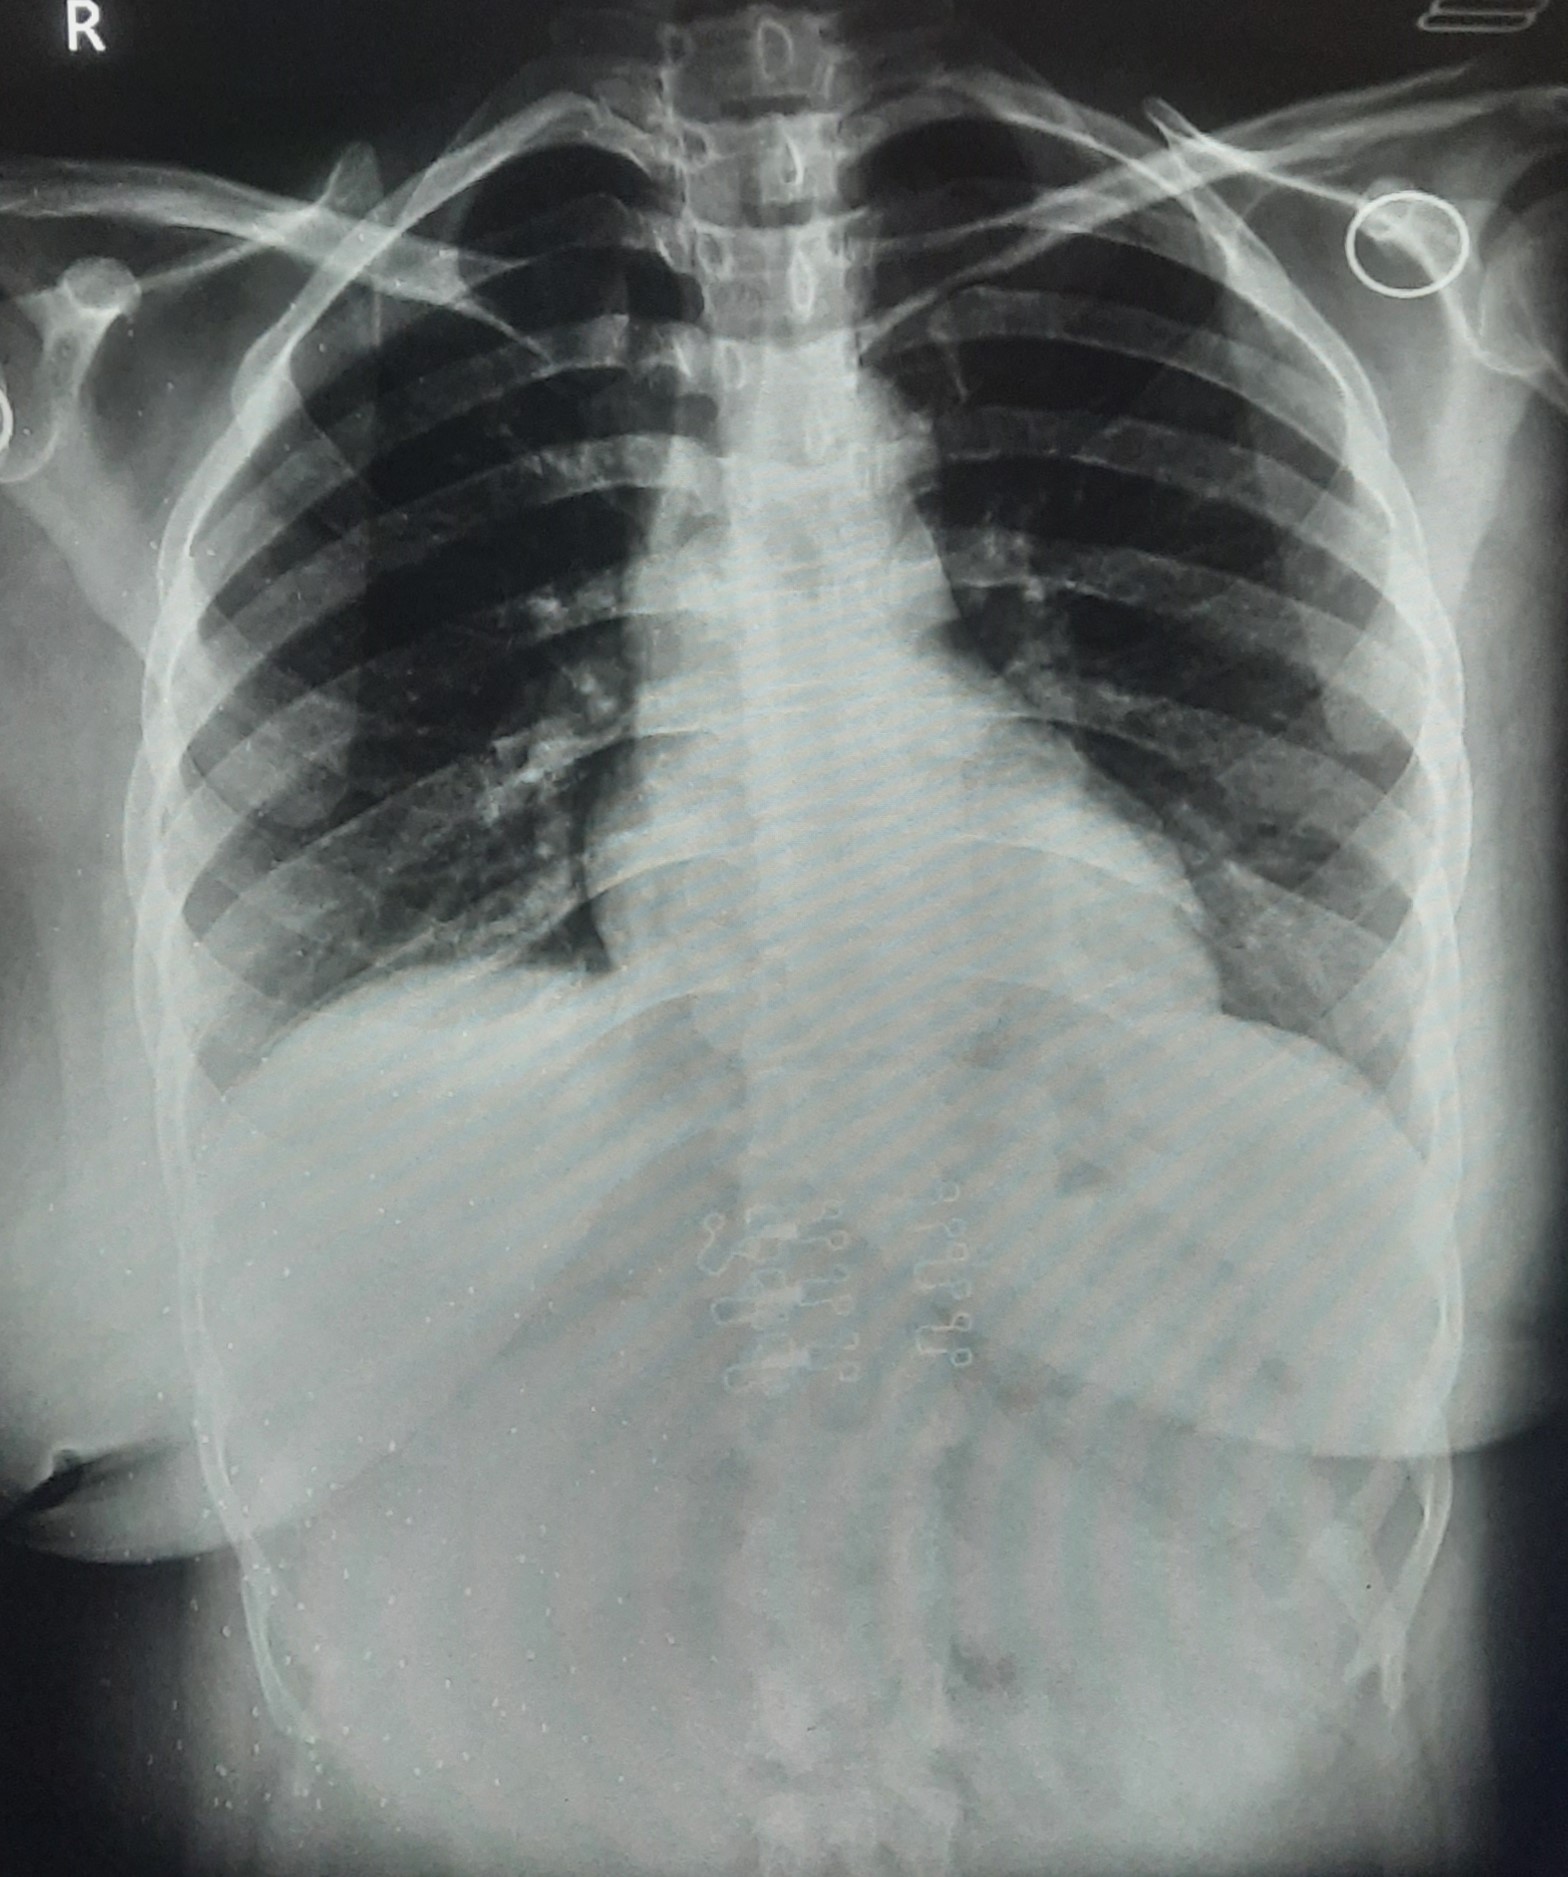

| IGGMC, Nagpur | 29-4206 | IGGMC, Nagpur | Rachana Sakhare | H/O subtotal hysterectomy Done On April, 2023 |

| Chest X-Ray Image |